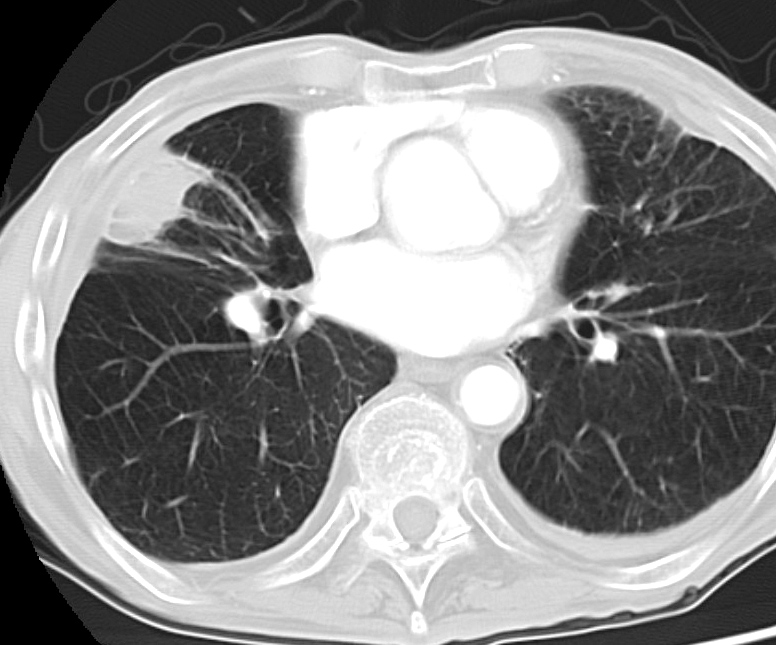

Rounded atelectasis case 3